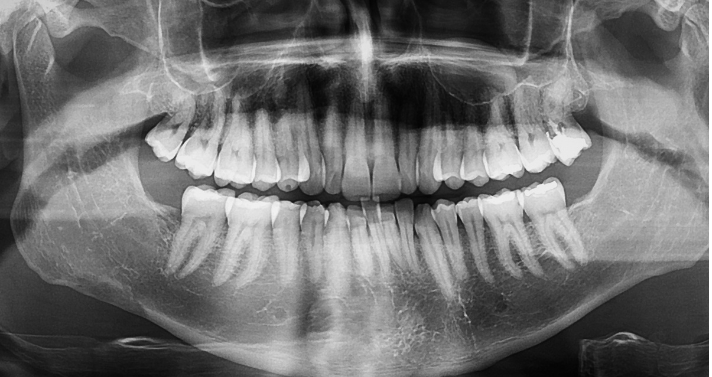

A regular dental X-ray is flat. It shows your teeth from one angle, like a photograph. But your jaw isn’t flat. Your roots curve. Your sinuses dip. Nerves run through bone in paths you can’t see on a 2D image.

3D dental imaging captures your entire mouth in a rotating scan that takes about 20 seconds. The result is a full three-dimensional model of your teeth, bone, nerves, and soft tissue. We can spin it, slice it, zoom in on any spot. It’s the difference between looking at a map and actually walking through the building. At our Tracy office on N Tracy Blvd, we use this technology daily because it changes how we plan treatment.

A regular X-ray gives you a flat, single-angle view. A 3D scan captures your full jaw, roots, nerves, and bone in a rotating image you can zoom and slice from any direction. That matters when you have curved roots, hidden infections, or a nerve sitting close to a wisdom tooth. Flat images often look normal even when something is wrong. The 3D scan finds what the flat image misses.